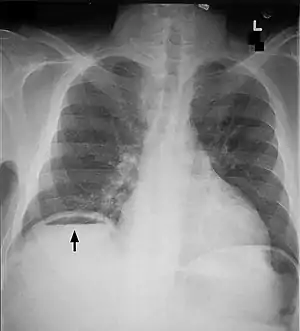

Another pneumoperitoneum on chest X-ray.